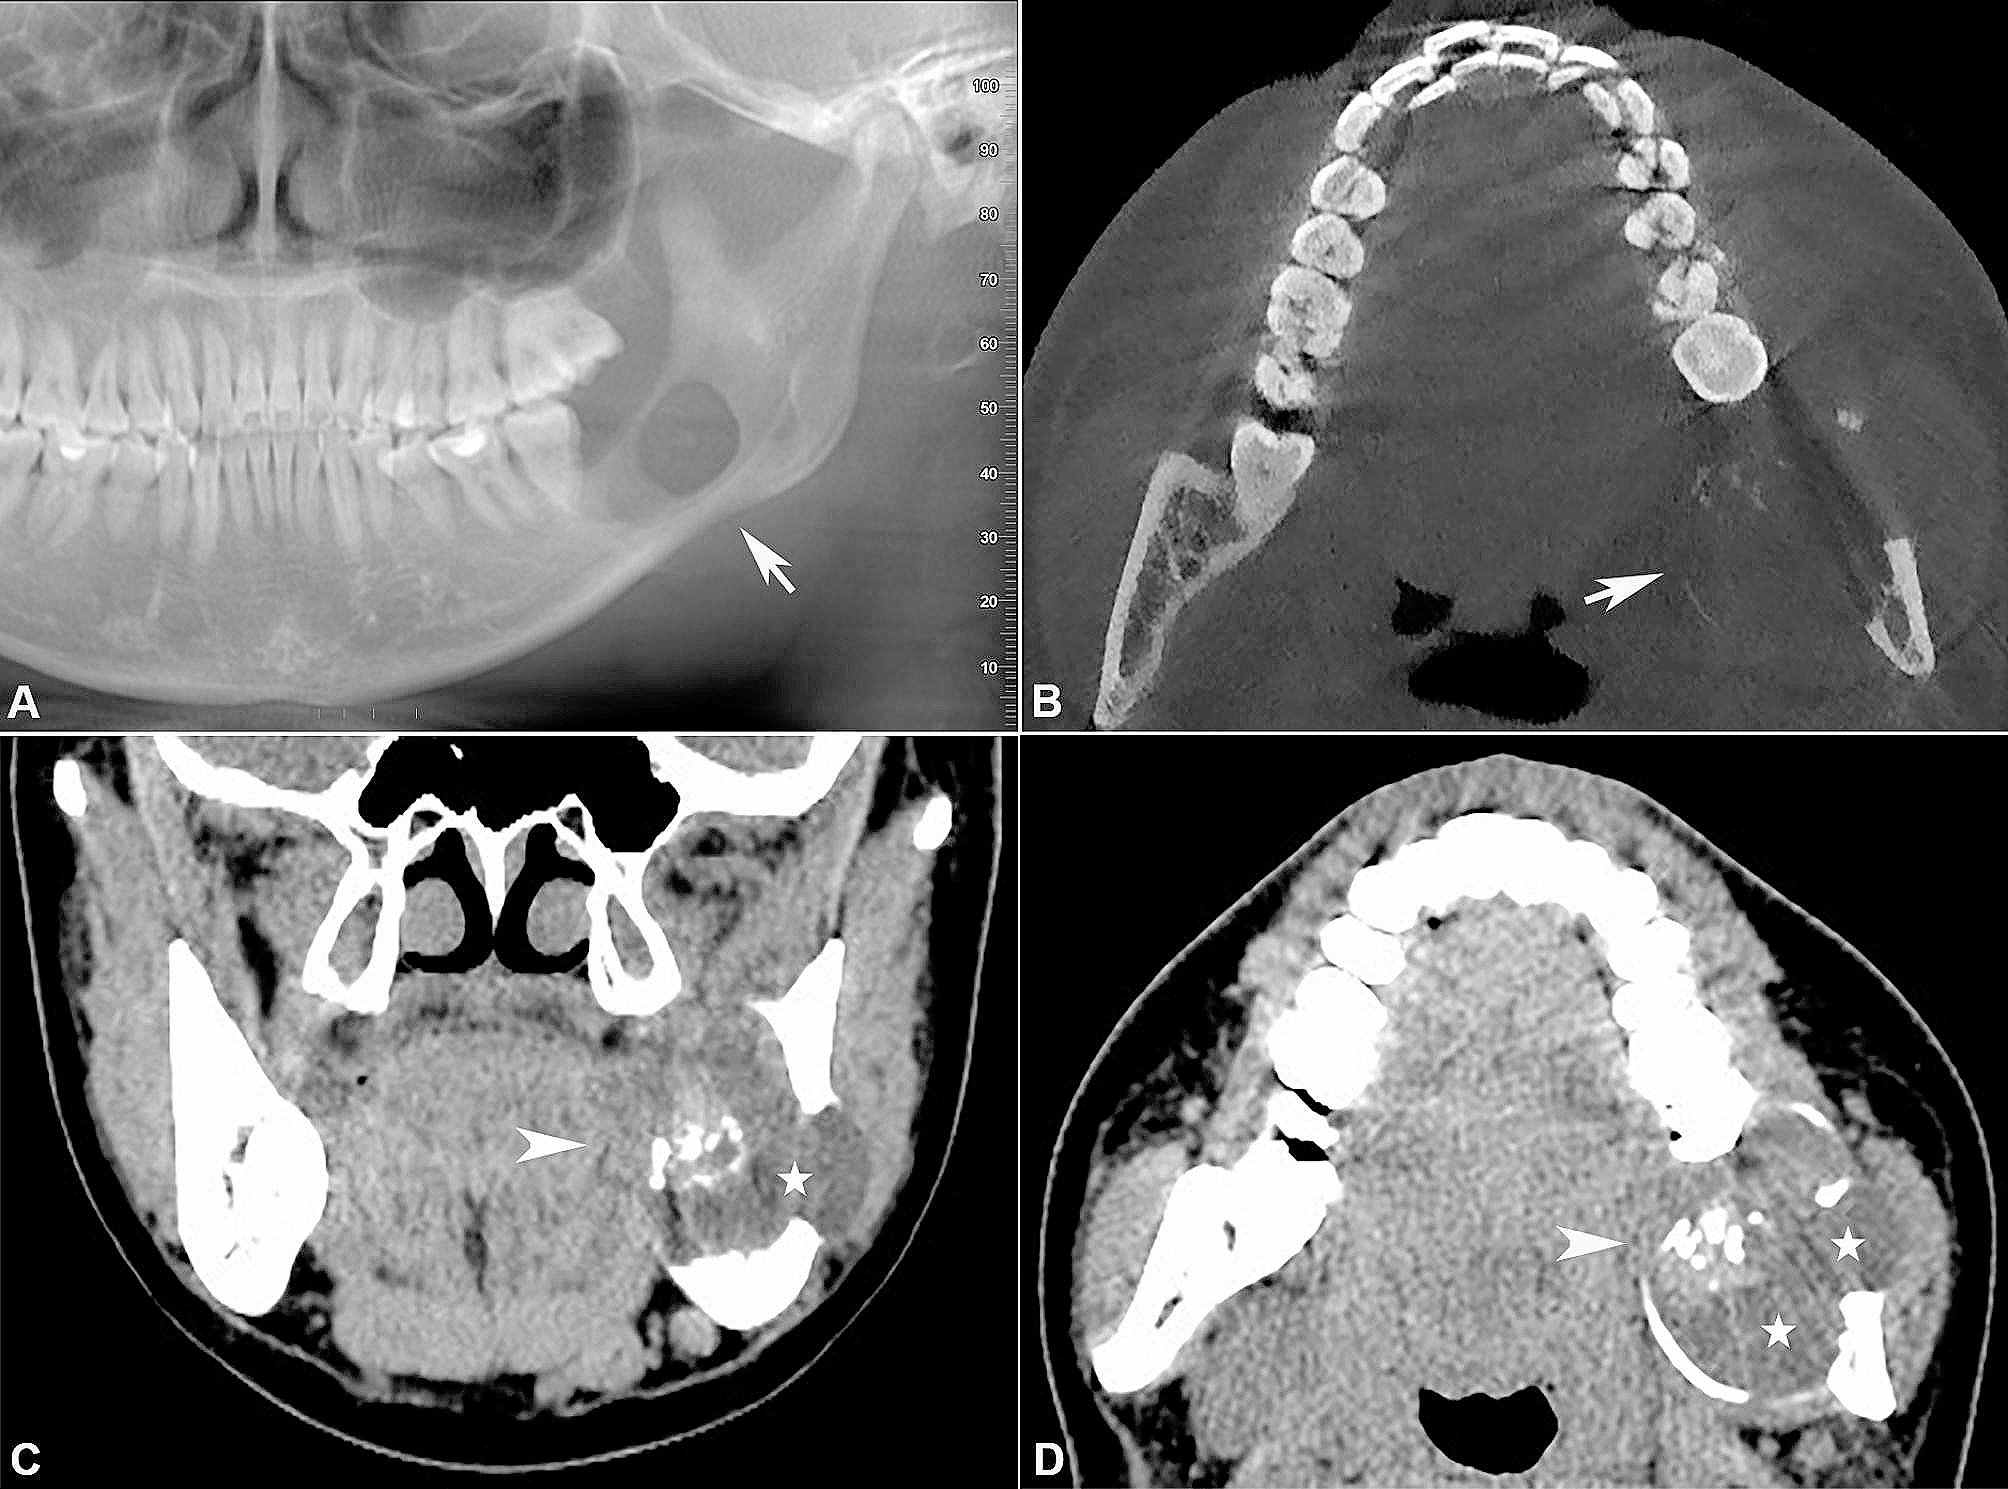

Hasil pemeriksaan radiografi. Tampilan panoramik yang telah direkonstruksi (A) dan pada tampilan aksial (B) terlihat adanya satu ruang lesi (unilokular) dengan batas yang jelas, tampak sebagai area berwarna gelap (radiolucent) yang berisi bahan padat berwarna terang (radiopaque) di bagian belakang rahang bawah sebelah kiri. Lesi tersebut menyebabkan pelebaran yang cukup besar dan juga penipisan hingga berlubang pada dinding tulang bagian luar (bukal) dan dalam (lingual) rahang bawah (ditunjukkan dengan panah). Pada tampilan koronal (C) dan aksial (D) terlihat adanya massa dengan batas yang jelas dan tampak tidak seragam. Massa tersebut terdiri dari bagian padat (ditunjukkan dengan kepala panah) dan bagian berisi cairan atau kistik (ditandai dengan bintang). Terlihat juga adanya endapan kalsifikasi yang tampak jelas pada gambar.